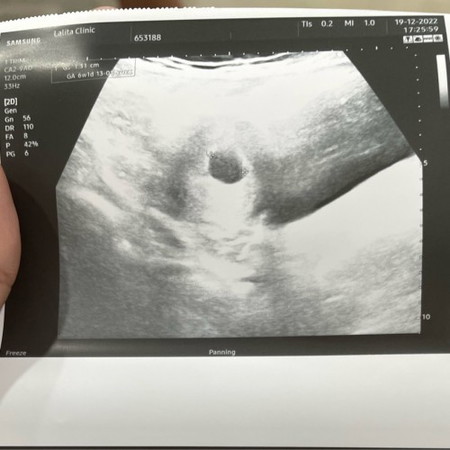

แม่พึ่งท้องได้5w+1d ค่ะ คุณหมอบอกว่าเห็นถุงตั้งครรภ์มดลูกปกติ

บ้านนี้ตรวจครั้งแรก 5w เหมือนกันค่ะ แล้วคุณหมอก็นัดอีกทีตอน 8w คราวนี้ชัดเลยค่ะทั้งตัวทั้งเสียงหัวใจ 🥰